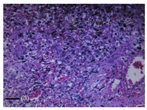

基于上述结果,术前诊断为脾脏良性肿瘤,随后进行了脾脏切除手术,术后病理检查,大体:脾脏切开见6 cm×5 cm×4 cm肿物,切面呈暗褐色,与脾组织分界不清。镜下:见大量异型内皮细胞构成不规则血管组分(图2)。免疫组化显示血管内皮细胞标记CD31、CD34、FLI-1、FVIII阳性,角蛋白系列、粒细胞和单核细胞标记CD15、S-100、淋巴细胞标记CD30阴性,Ki-67 20%。最终病理诊断为脾血管肉瘤(primary splenic angiosarcoma,PSA)。借鉴其他PSA早期肿瘤治疗经验,患者术后未进行辅助治疗。术后常规随访,最近随访是在术后1年,无复发征象,未出现手术相关近期或远期并发症,生活质量同术前无明显改变。